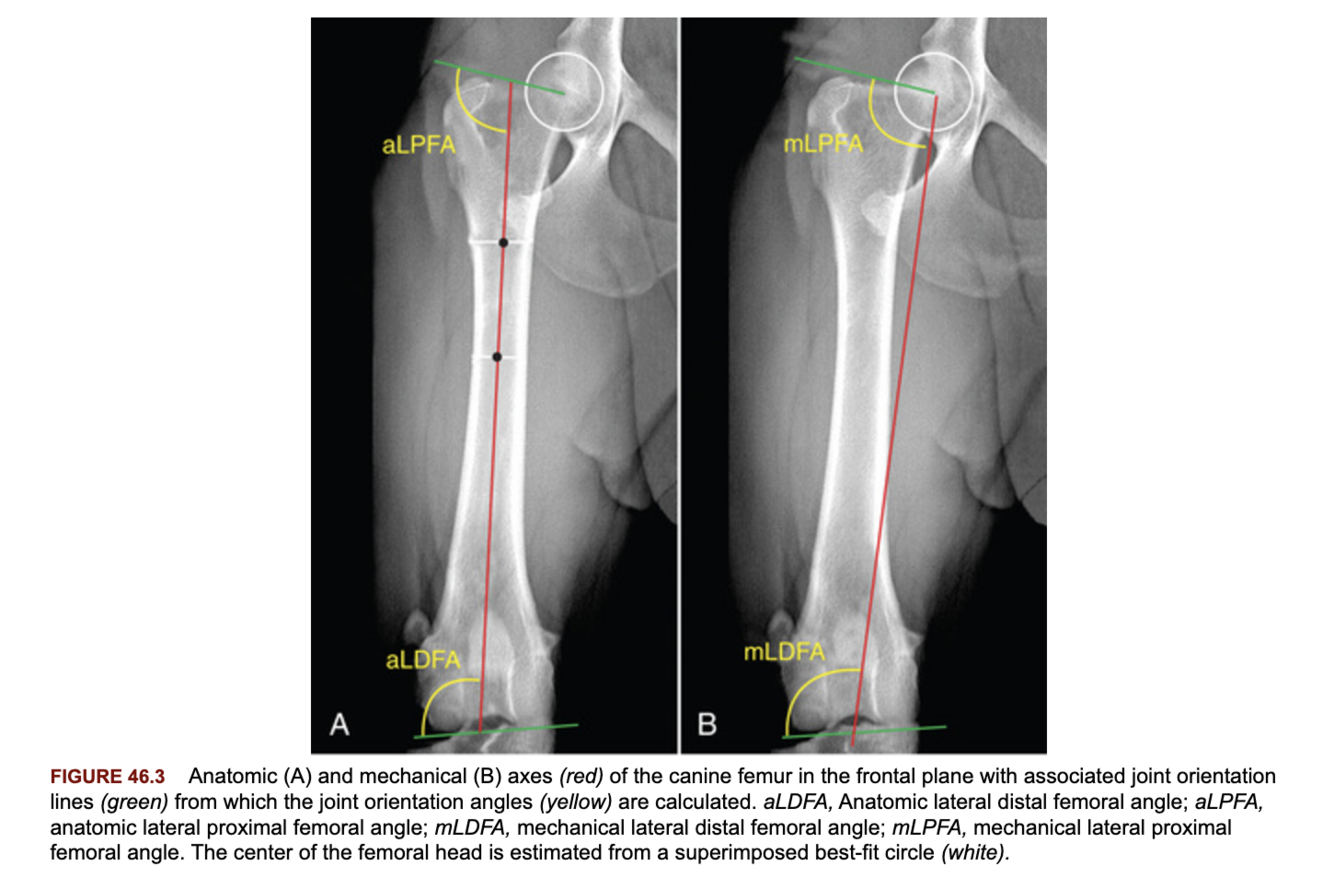

What is the difference between the anatomic and mechanical axes of the bone?

A

Anatomic: a line that passes through the center (or mid-diaphysis) of the bone in the frontal or sagittal plane.

Mechanical: a line that passes through the center of the proximal and distal joints (may be more clinically useful than the anatomic axis for sigmoidal bones such as the tibia, humerus).

Describe how the joint orientation lines and anatomic axis of the femur are determined?

Frontal plane: joint line distally, center of the femoral head to the proximal greater trochanter proximally.

Anatomic axis: determined by a line that connects points measured 33 and 50% distal to a point at the proximal margin of the femoral neck.

Q

What are the normal joint orientation angles for the femur?